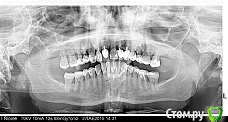

Oxsana Опубликовано 27 мая, 2015 Поделиться Опубликовано 27 мая, 2015 Небольшая подвижность и глубокий пародонтальный карман, есть ли смысл его лечить. Снимки прилагаю. Прокомментируйте, пожалуйста. сотник.bmp Ссылка на комментарий

Oxsana Опубликовано 27 мая, 2015 Автор Поделиться Опубликовано 27 мая, 2015 Сегодня была у терапевта. Она сказала, что ели сдерживается от глагола "удалить". Предложила кюретаж, лоскутную пластику. КТ для диагностики костной ткани. В предлагаемом вами варианте , при достаточном и необходимом количестве оставшейся ткани каковы гарантии(минимум лет) сохранения зуба.Спасибо. Ссылка на комментарий

faity Опубликовано 27 мая, 2015 Поделиться Опубликовано 27 мая, 2015 лоскут откидывается, кюретаж проводится, НКР с мембраной и ССТ, 1.5 и 1.6 в это время под временную реставрацию, через полгода смотрим результат, если все хорошо- постоянная реставрация Ссылка на комментарий